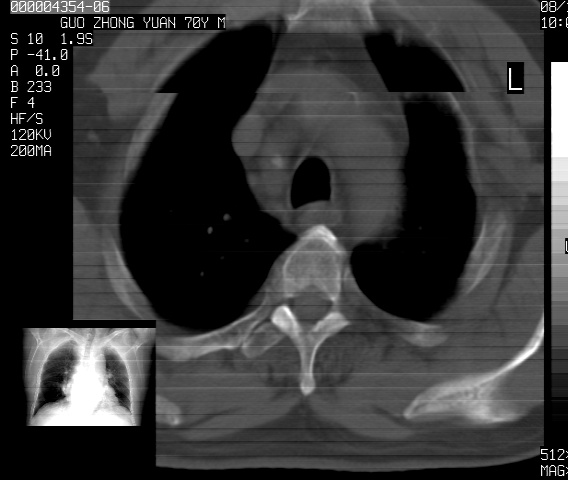

以下是引用sdzyy在2008-12-1 11:49:00的发言:[br]图像不全,请上传,右下肺炎症可能性大,占位待排.

以下是引用zjzjr在2008-12-1 14:53:00的发言:[br]图像不全,请上传,右下肺炎症可能性大,占位待排.心影增大,建议进一步检查.